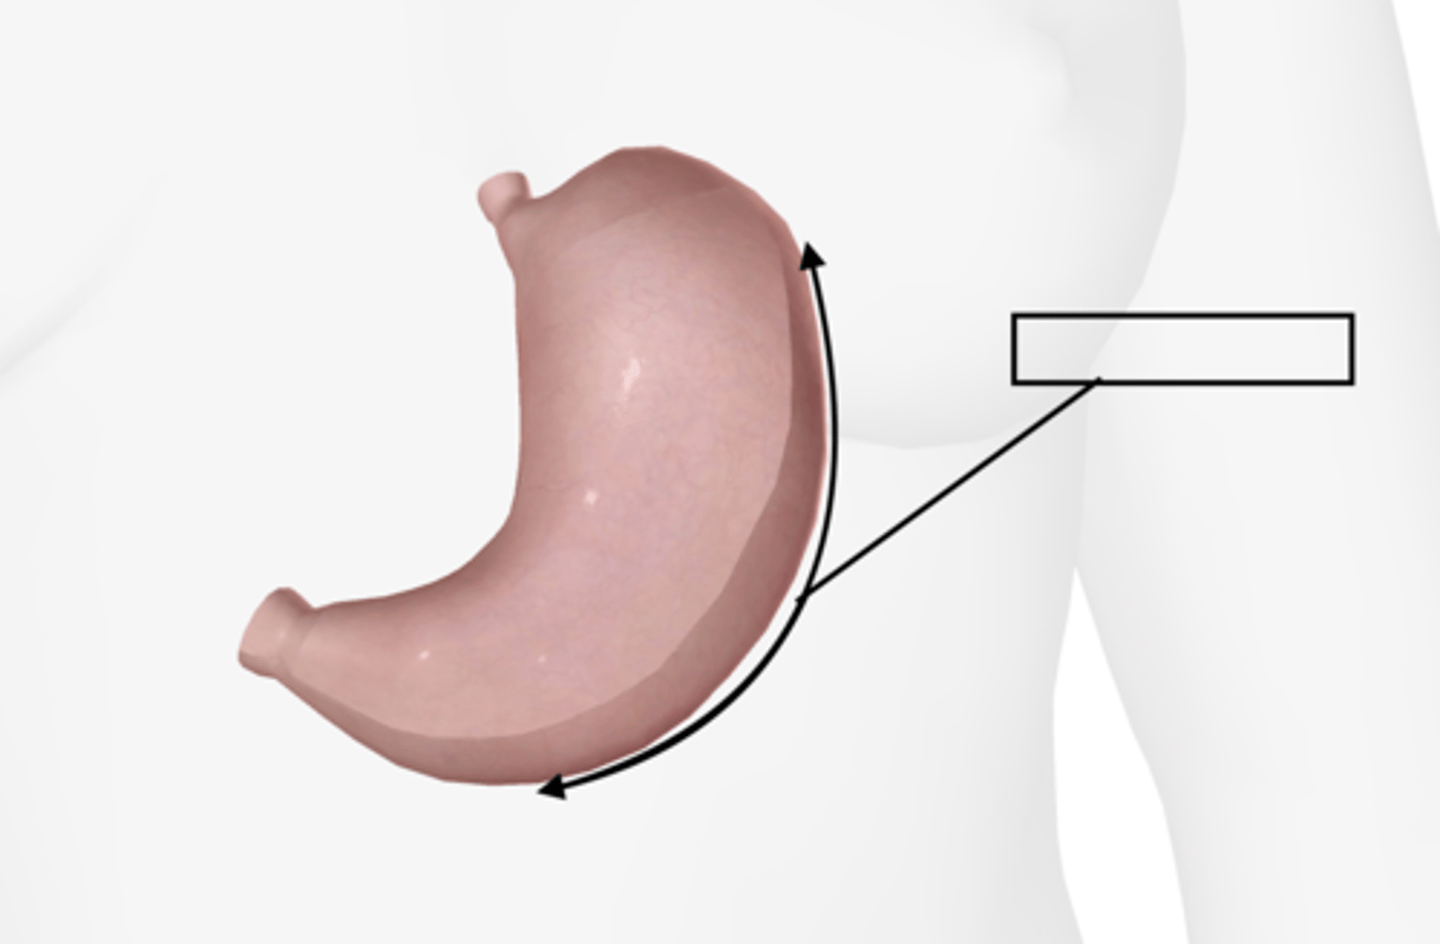

Stomach

Lesser curvature

Greater curvature

Cardiac sphincter

Pyloric sphincter